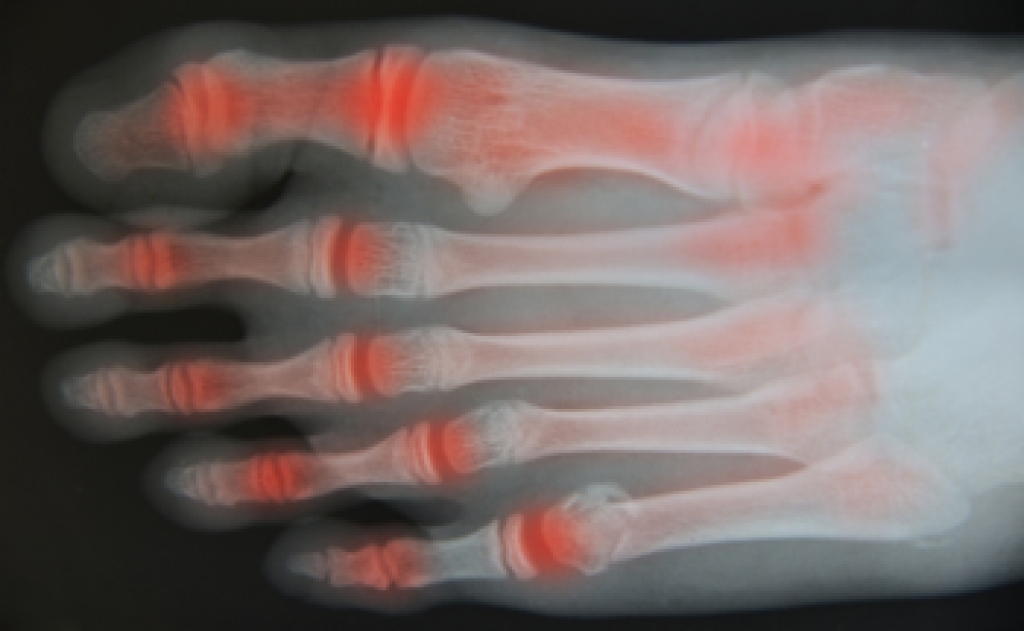

Arthritis in the Foot

Arthritis can occur in any joint in the body, including in the feet. Common types of arthritis in the foot are osteoarthritis, rheumatoid arthritis, and gout. The big toe is usually where arthritis occurs in the foot; this is known as hallux rigidus.

The most common form of joint replacement in the foot is a first metatarsophalangeal (MTP) joint placement. MTP joint replacement surgery is designed to treat hallux rigidus. Surgery is not intensive, and recovery occurs within one to two months after the procedure has been done. Overall, joint replacement surgery is a safe and effective way to treat pain in the joint of the foot.